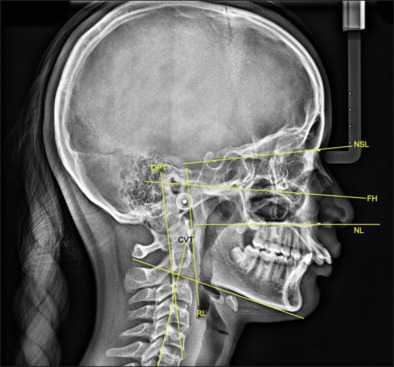

Methodology: A retrospective analysis was undertaken using the pre- and post-treatment records of 35 skeletal class II patients who used the FFRD to achieve class II correction. The metrics suggested by Solow and Rocabado were used to evaluate the cranial and cervical positions. Eleven angular parameters were evaluated to determine the relationship between the mandibular ramus and the skull as well as the upper and middle craniocervical positions. To compare the parameters before and after fixed functional therapy, a Wilcoxon signed rank test was used.